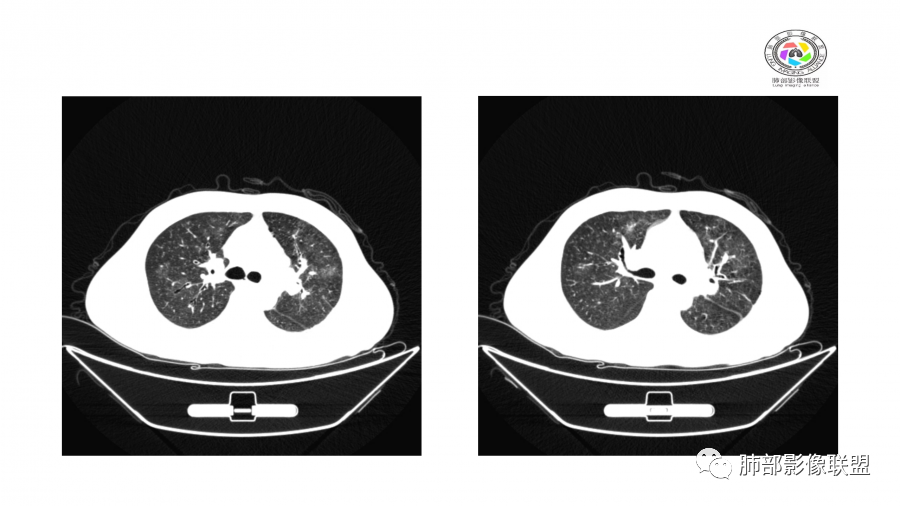

一月后:

南边:

病灶此起彼伏